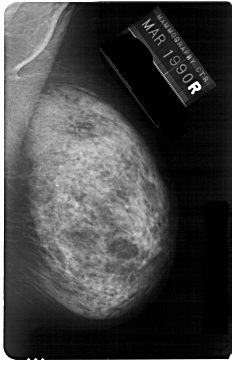

A_1148_1.RIGHT_MLO

RIGHT_MLO LINES 5491 PIXELS_PER_LINE 3466 BITS_PER_PIXEL 12 RESOLUTION 43.5 NON_OVERLAY